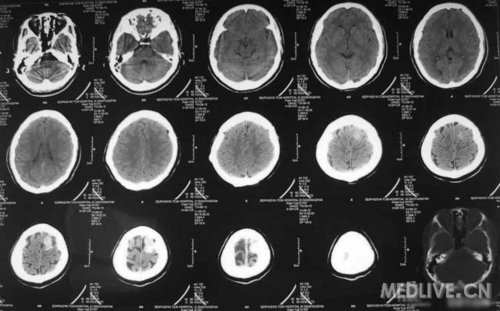

患者女,56岁,因右侧肢体活动不利2天于2011-06-15入院。查体:神志清,精神可,右侧肢体肌力4级,余无阳性体征。CT示左额叶占位,脑膜瘤可能性大。MRI示左额镰旁脑膜瘤,脑干左半亚急性梗塞。给予活血、神经营养、对症治疗,现一般情况好。请高手指点,何时手术切除脑膜瘤好啊?